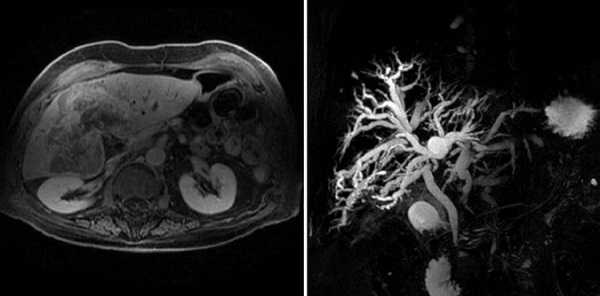

Холангиокарцинома на снимках МРТ

Стол с пациентом перемещается в трубу томографа, детекторы фиксируют реакцию тканей и транслируют информацию на монитор компьютера. Сканирование проводят в сагиттальной, фронтальной и аксиальной проекциях. На основании послойных изображений врач может реконструировать 3D-модель гепатобилиарной системы.

Исследование желчевыводящих протоков с помощью магнитно-резонансной томографии является высокоточным и эффективным методом диагностики заболеваний билиарной системы. МРТ холангиография что показывает? С помощью процедуры выявляют:

Метод отличается высокой информативностью. Томограммы визуализируют состояние печеночного, пузырного, панкреатического протоков, отражают состояние окружающих тканей и кровеносных сосудов. Преимуществом МР-холангиографии является безопасность и отсутствие ионизирующей лучевой нагрузки.